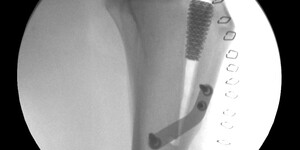

- ortopedie, traumatologie, totální endoprotézy kyčelních kloubů